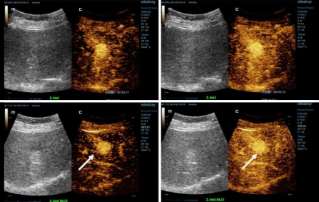

![HiFR CEUS ile Daha Kesin Tan?lar]() HiFR CEUS ile Daha Kesin Tan?larKontrastl? ultrason (CEUS) ?ok dinamik bir aland?r ve son birka? y?lda teknolojik yenilikler g?r├╝nt├╝ kalitesini daha da art?rm??t?r. Bu yeniliklerden biri, ayn? anda geleneksel ultrasona g?re on kata kadar daha fazla g?r├╝nt├╝ ├╝retebilen y├╝ksek ?er?eve h?zl? kontrastl? ultrasondur (HiFR CEUS).Ultrason | Genel g?r├╝nt├╝leme 2022-12-16

HiFR CEUS ile Daha Kesin Tan?larKontrastl? ultrason (CEUS) ?ok dinamik bir aland?r ve son birka? y?lda teknolojik yenilikler g?r├╝nt├╝ kalitesini daha da art?rm??t?r. Bu yeniliklerden biri, ayn? anda geleneksel ultrasona g?re on kata kadar daha fazla g?r├╝nt├╝ ├╝retebilen y├╝ksek ?er?eve h?zl? kontrastl? ultrasondur (HiFR CEUS).Ultrason | Genel g?r├╝nt├╝leme 2022-12-16 -